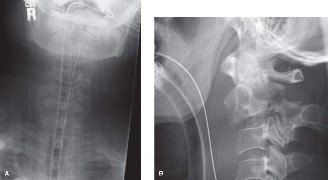

A 63-year-old male sustained a hyperextension injury to his neck while diving into a pool. Upon presentation,…